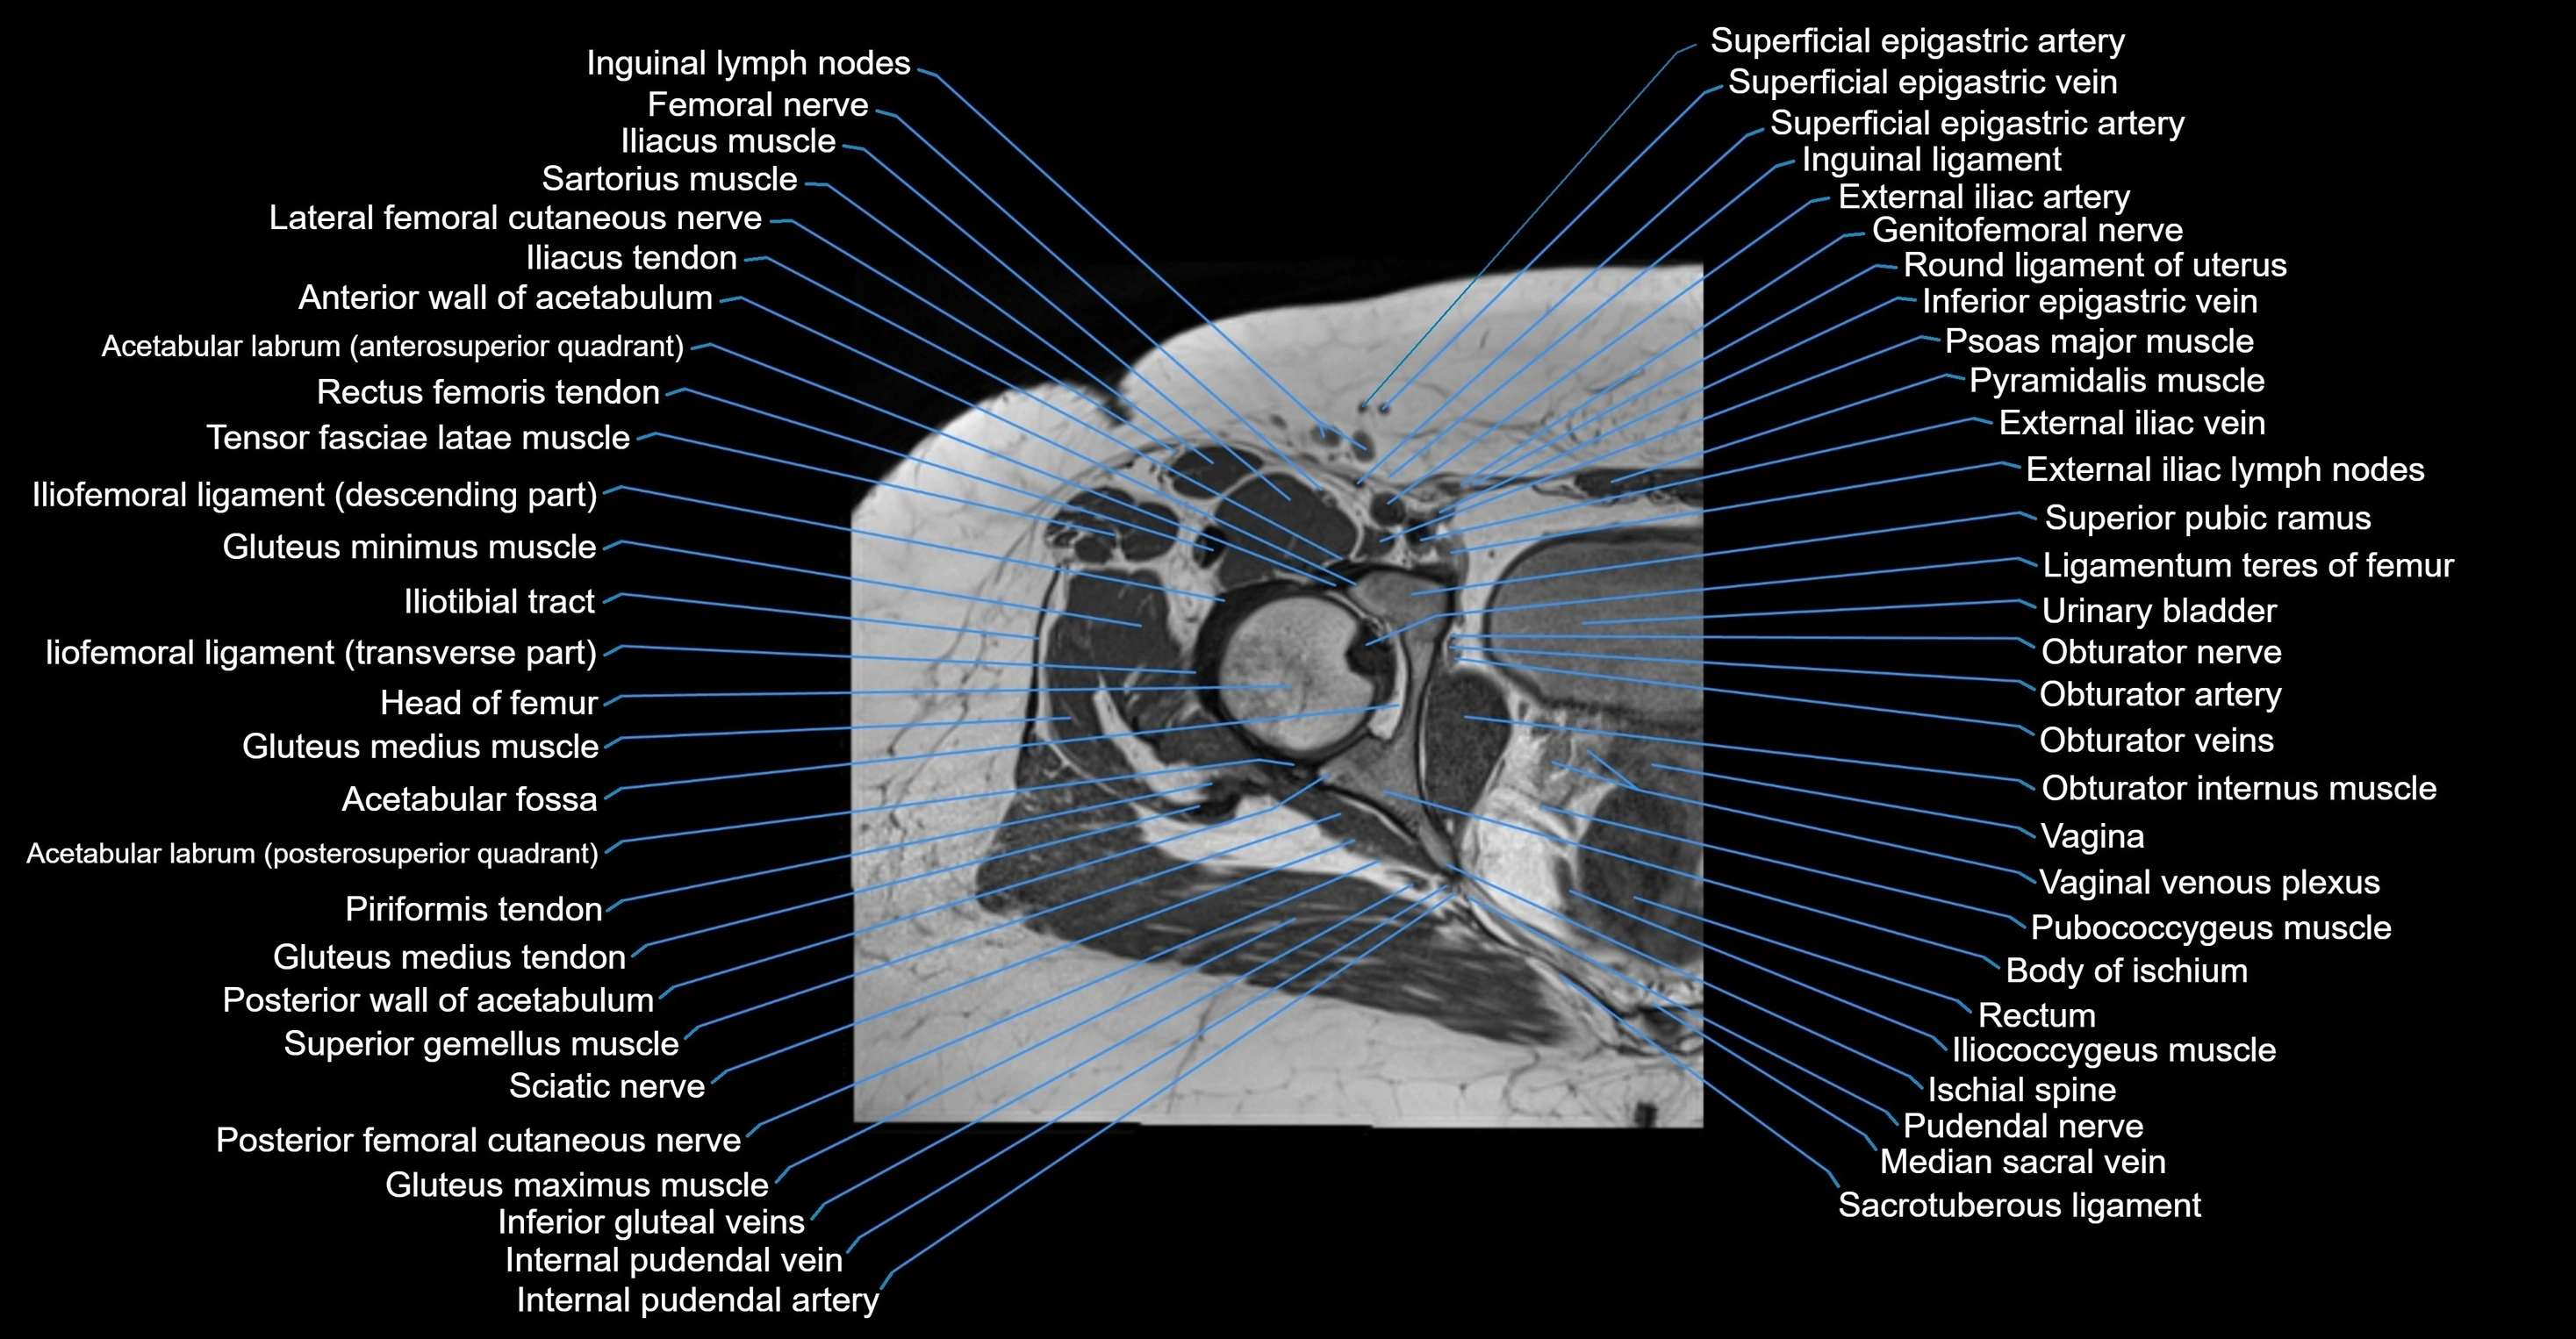

- Head of femur

- Iliofemoral ligament

- Iliofemoral Ligament inferior band (vertical band, medial band)

- Iliofemoral Ligament superior band (transverse band, lateral band)

- Iliotibial tract

- Vagina

- Vaginal venous plexus

- Pubococcygeus muscle

- Iliococcygeus muscle

- Ischial spine

- Pudendal nerve

- Median sacral vein

- Sacrotuberous ligament